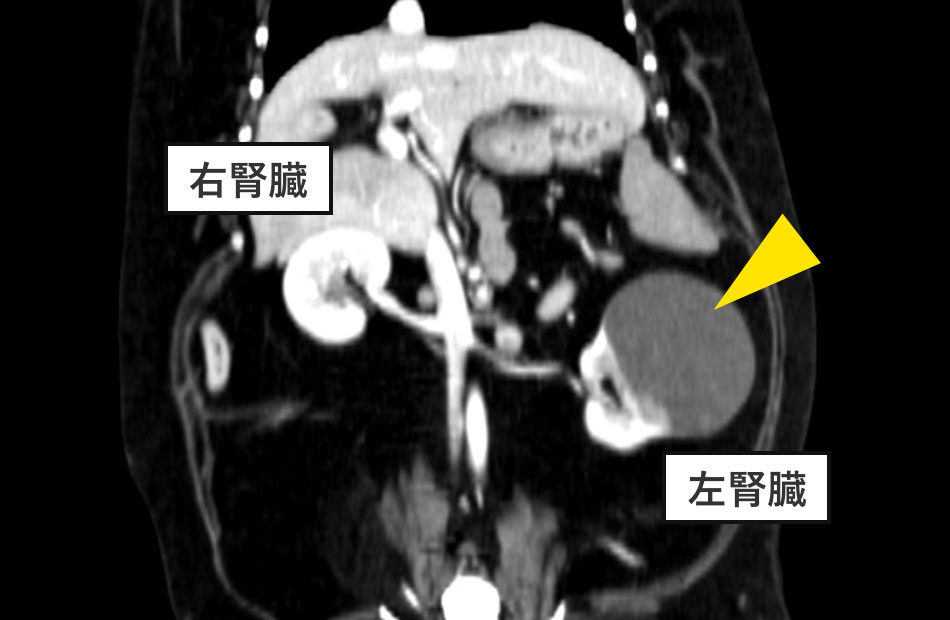

CT検査

左腎の頭側に隆起した嚢胞構造(最大5.7cm)を認めました(図:黄矢印が腫瘤を含む嚢胞)。

検査結果から、「左腎の腎臓腫瘍」と診断しました。血液検査の結果およびCT造影検査により、正常と思われる対側にある右腎臓の腎臓機能は問題がないと判断したため、体調の悪さの原因の1つと考えられる腫瘍のある左腎臓の摘出を計画しました。